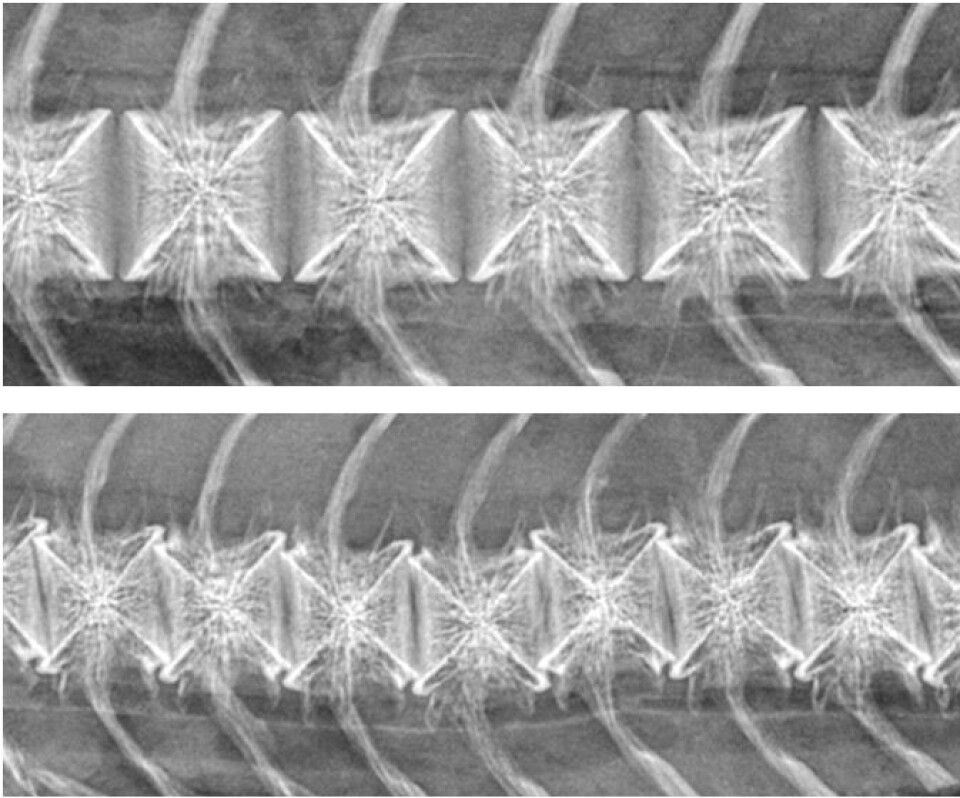

Høsten og vinteren 2016-17 kom det meldinger om en ny type ryggdeformitet hos slaktefisk som oppdretterne mistenkte hadde sammenheng med bruk av en ny vaksine mot PD. Deformitetene var spesielt alvorlige, med mange unormale virvler per fisk, tap av tilvekst og nedsatt filetkvalitet. På røntgen skilte disse misdannelsene seg klart fra andre typer feil i ryggrad, og de ble kalt «korsstingsvirvler» for å kunne skille dem fra andre og mer vanlige misdannelser.

Fisken i forsøket utviklet seg normalt, med god vekst og lite dødelighet, fram til slakting ved en snittvekt på 3,8 kilo. Det var ikke noe å se på røntgen før i det siste uttaket. Der var det et tydelig, om enn lavt, innslag av korsstingsvirvler i de to PD-vaksinerte gruppene, og ikke i de to andre.

I vevsundersøkelser (histologi) fant forskerne tydelige forandringer i vekstsonen i virvlene i perioden etter vaksinering. Det var økt avleiring av proteinet fibrin og en tydelig økt uregelmessighet i de beinproduserende cellene i vekstsonen. Etter hvert som fisken vokste ble det dannet normalt bein videre, mens den svakheten som var dannet i perioden etter vaksinering ble liggende på det stedet der den var dannet. Ved slakt fant forskerne de typiske korsstingsforandringene med røntgen og histologi. Kontrollmålinger på røntgenbilder viste at den ringformede bruddsonen som var dannet konsekvent lå på det stedet der virvlenes veksoner var på tidspunkt for vaksinering.